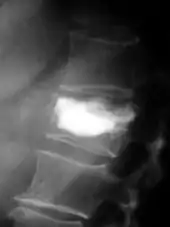

- Vues de fractures pathologiques

Fracture pathologique de l'humérus sur une métastase de carcinome du rein